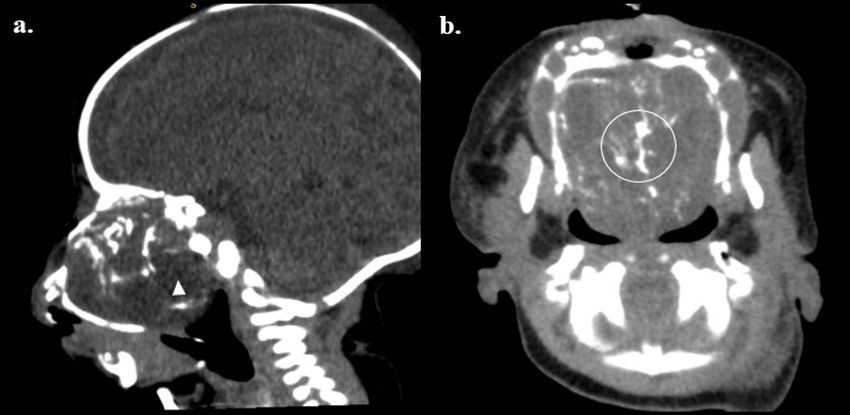

Durante la hospitalización de la recién nacida se realizó tomografía de senos paranasales y órbitas, la cual mostró:

Una masa sólida heterogénea de 39 x 50 milímetros, con calcificaciones internas y algunas regiones intratumorales de comportamiento graso, con epicentro en la cavidad nasal, de aspecto expansivo que remodela la cavidad nasal y celdillas etmoidales, que invade y remodela la cavidad oral, reduce en la profundidad de las órbitas generando hipertelorismo y leve grado de proptosis ocular. (Figura 3).